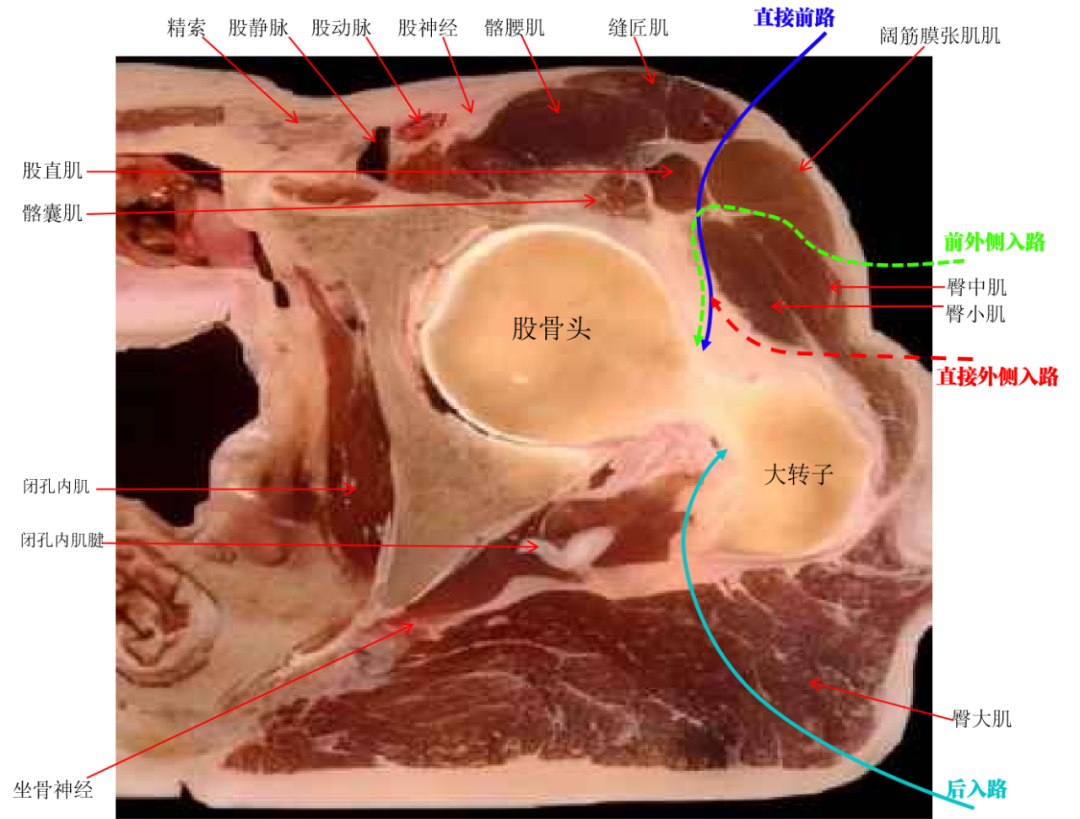

髋关节置换常用入路比较

前路置换切口明显缩短,从缝匠肌和阔筋膜张肌间隙进入,术后无需肌腱重建,且后方关节囊完整;术后疼痛轻,脱位风险较低,术后一周内即可练习下蹲。

对于大多数关节挛缩病人来说,前路更方便松解;在某些肥胖患者中,前路也更容易接近髋关节。

但缺点是绝大多数医生学习关节置换技术都是从后路开始,入手前路则需要一段时间的重新适应,改变思维,改变术中把控假体角度的习惯。

另外,对于肢体短缩、屈曲挛缩的病例,前路关节置换复位过程比后路要容易得多,同时减少了牵引过程中对坐骨神经的牵拉。点击下图查看复位难易程度: